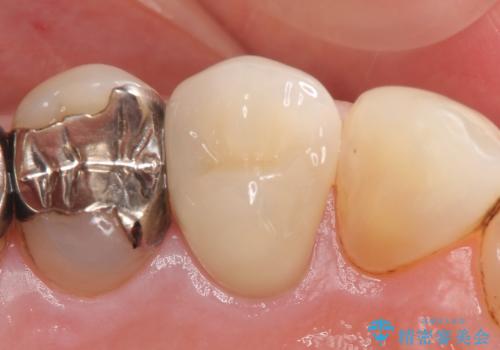

- 右上4番目の歯がなにもしなくてもズキズキ痛むといらっしゃった方の症例です。

検査の結果持続痛も認めたため、虫歯除去後根管治療を行いました。

その後オールセラミッククラウン(エクセレント)による補綴を行いました。

- オールセラミッククラウン(エクセレント)…¥180,000、仮歯…¥10,000、ファイバーコア…¥20,000費用は治療当時の料金となります